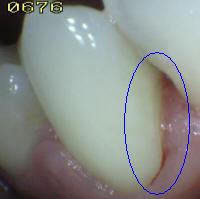

- Secar con jeringa triple por 5 segundos para

realizar el examen visual en seco